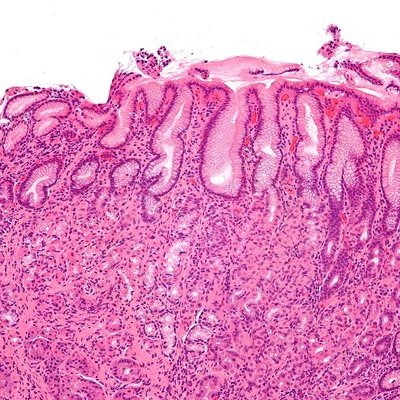

Врач-гастроэнтеролог Анастасия Чижикова указала основные причины гастрита, подчеркнув, что хронический стресс может быть его вызывающим фактором. Гастрит представляет собой заболевание, приводящее к повреждению слизистой оболочки желудка и возможному развитию хронической формы, являющейся предпосылкой для язвенной болезни или рака.

Чижикова выделила внешние и внутренние факторы, включая инфицирование Helicobacter pylori, нерегулярное питание, стресс, алкоголь и курение. Она также подчеркнула вред от употребления раздражающих слизистую оболочку продуктов, лекарств и воздействия радиации.